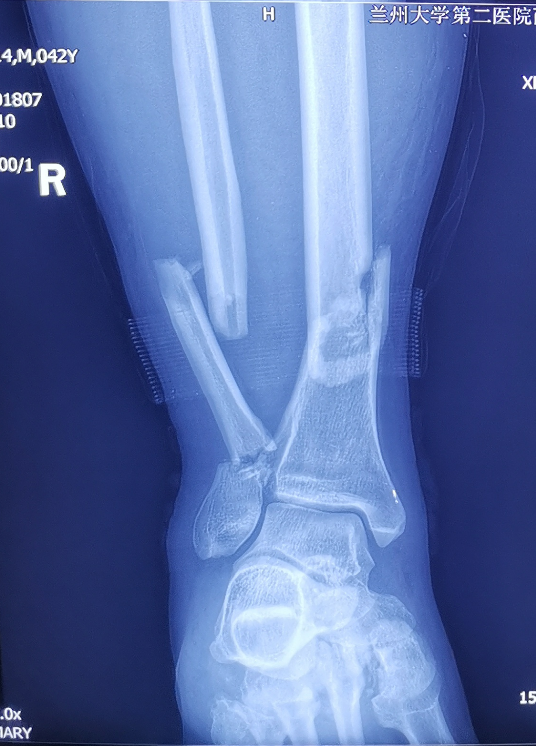

患者,男,42岁,因异物砸伤致右下肢疼痛、肿胀,活动障碍7小时入院。入院后诊断为右胫腓骨远端骨折、右足楔骨骨折、右跖骨骨折、右骰骨骨折。入院时右侧小腿远端前内侧明显肿胀,局部可见大量张力性水泡。骨科四病区医护人员立即开展病情讨论,并制定详细周密的手术计划,同时在患者及其家属知情同意后,实施胫骨远端骨折逆行胫骨髓内钉内固定术。

小腿远端腓骨骨折治疗多采用切开复位钢板内固定,胫骨骨折可选用MIPPO技术钢板固定、胫骨顺行髓内钉及胫骨逆行髓内钉技术,其中MIPPO技术因患者软组织条件差术前消肿时间过长,顺行髓内钉因骨折线位置较低髓内钉远端把持力不足,同时会一定程度影响膝关节活动。而胫骨逆行髓内钉技术作为国内逐渐发展起来的新技术,在处理胫骨远端骨折时具有软组织损伤小、复位及固定简易等优势,十分适合本症状患者。